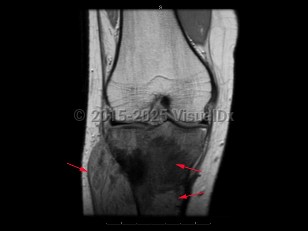

Osteosarcoma in Child

The most common malignant tumor of bone. It arises from osteoblastic cells. Patients typically present with bone pain or a mass. The long bones are most commonly affected, and the tumor frequently metastasizes to other locations, especially the lung. Osteosarcoma is most common in males under 30 years of age. It can also occur secondary to medical conditions such as Paget disease and prior radiotherapy. Osteosarcoma is treated with chemotherapy and surgical excision of the primary tumor. With treatment, overall survival is approximately 60%-80%.